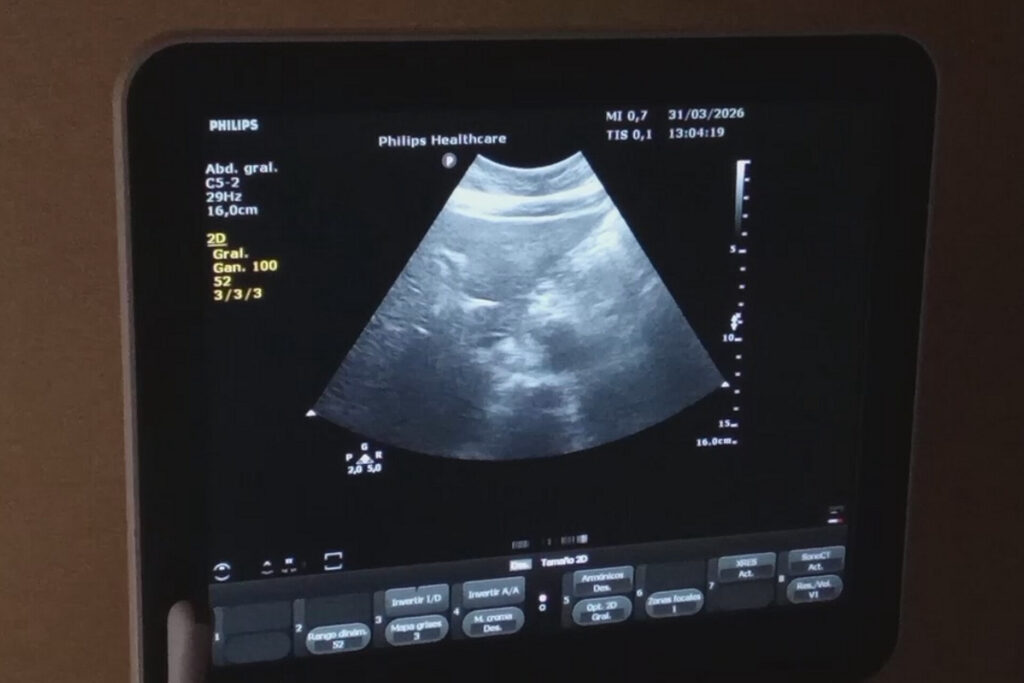

El servicio de Medicina Hiperbárica y Subacuática, una planta de oxígeno, la sala de fisioterapia y rehabilitación, el taller de prótesis, la sala de medicina tradicional y el servicio de imagenología ponen en alto el nombre de la institución hospitalaria.

Respecto al Servicio de Imagenología la M. Sc. Caridad Aragón Sánchez, Jefa del mismo, explicó que cuentan con la tecnología para realizar las diferentes pruebas y resaltó la importancia de la especialidad en el diagnóstico de las enfermedades o padecimientos.